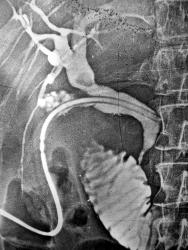

Механическая желтуха, УЗИ еще не было. Лапараскопическая холецистостомия, через свищь - двойное контрастирование билиарного тракта. Какова причина мех. желтухи?

Циркулярное сужение до полной непроходимости в области дистальных отделов общего желчного протока, симптомчик "перевернутой тройки" - наблюдение классической опухоли.

Здравствуйте! Дабы не тратить много контрастного вещества при мех желтухе с растянутым билиарным трактом - по дренажу в ж. пузырь вводили 40 - 60 мл. любого водорастворимого препарата в положении на левом боку, чтобы препарат ушел в интересующую нас зону, а потом продували воздухом, шприцом, около 60 - 100 мл, и воздух естественно уходил вверх - в протоки печени... (в данной ситуации они нас особо не интересовали). Так что цель введения воздуха - уменьшить объем вводимого контрастного вещества.

Да очень похоже на рак терминального отдела холедоха. Для наглядности пример из нашего архива начала 80-х годов (отсутствие приличных УЗИ и КТ). Рак терминального отдела холедоха с верификацией после операции (такие опухоли можно оперировать, в отличие от рака головки ПЖ, где исход при похожей картине будет не очень хорошим).

На первой ангиограмме- целиакография после введения 10 мкг адреналина(фарм проба) - сегментарные артерии печени спазмируются, в проекции терминального отдела холедоха увеличенные артерии(передние панкреато-дуоденальные), которые снабжают опухоль (стрелка). На втором снимке сочетанная чрескожная чреспеченочная холангиография (через иглу Шиба 0.7 мм диаметром) и целиакография- виден дефект наполнения в терминальном отделе, расширение холедоха и желчного пузыря.

Сдавление холедоха извне, черное пятно - желчный пузырь раздутый воздухом в ортоградной проекции.